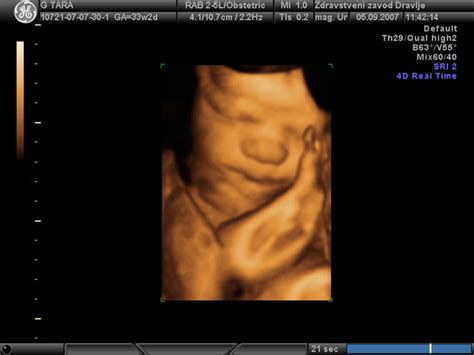

Utripanje v trebuhu med nosečnostjo je lahko posledica več dejavnikov, ki so povezani tako z otrokovim razvojem kot s fiziološkimi spremembami v telesu matere. Ena najpogostejših razlag za ta občutek je kolcanje ploda. Kolcanje je normalna funkcija, ki se lahko pojavi že v drugem trimesečju nosečnosti, pogosto med 18. in 30. tednom. Čeprav je izraz "kolcanje" pogosto uporabljen, nekatere ženske ta občutek opisujejo kot ritmično utripanje ali tresenje, ki ga lahko čutijo v spodnjem delu trebuha. Ti ritmični gibi lahko trajajo nekaj minut in se lahko pojavijo večkrat na dan, včasih celo ponoči. Za otroka to ni neprijetno, nekateri strokovnjaki celo menijo, da je kolcanje koristno za razvoj določenih funkcij.